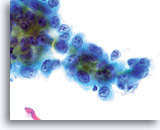

Adenocarcinoma in situ

Unterschiedlich große, dichte, hyperchromatische Zellverbände, die in der Übersichtsvergrößerung auffallen, machen eine genauere Beurteilung nötig.

20x

Bei starker Vergrößerung können diese Zellverbände/Sheets, atypische zytologische Merkmale und eine atypische Gewebearchitektur aufweisen. Dazu gehören: Zelldrängeln, Schichtenbildung, Rosettenbildung, Feathering, Hyperchromasie, variable Nukleoli und Unregelmäßigkeiten der Kernmembran. Das beständigste und auffallendste Merkmal ist das Zelldrängeln, wodurch die Kerne elongiert werden und wegen der hohen Zellteilungsrate gegeneinander “drücken”. Dies führt auch zur Stratifizierung der Kerne. Die Kerne können oft in allen Ebenen des Gewebefragments gesehen werden. Feathering kommt ebenfalls vor, es kann allerdings diskreter sein als im konventionellen Pap-Abstrich, wo es durch das Ausstreichen der Zellen überbetont wird. Beim ThinPrep® Pap Test sind Zellentnahme und –transfer viel schonender. Feathering ist eine Folge der Auflösung des Gewebeverbandes und erscheint im ThinPrep® Pap Test als Ausziehung des Zytoplasmas und der Kerne, welche aus dem Gewebefragment herausfallen. Da Zellen auch unter benignen Bedingungen so aussehen können, als ob sie sich vom zugehörigen Gewebsfragment trennten, sollte dieses Kriterium nicht alleine verwendet werden. Zur Diagnose eines AIS sind die entsprechenden Kernmerkmale erforderlich.